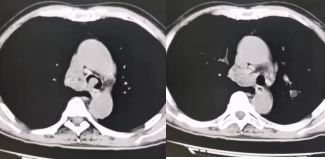

术前CT可见气管下端及右主支气管新生物阻塞管腔

术后CT见梗阻解除,气道通畅